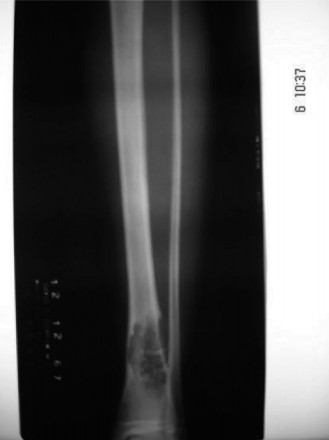

A 48-year-old female presents to your office with worsening right ankle pain. Twenty years ago she sustained …